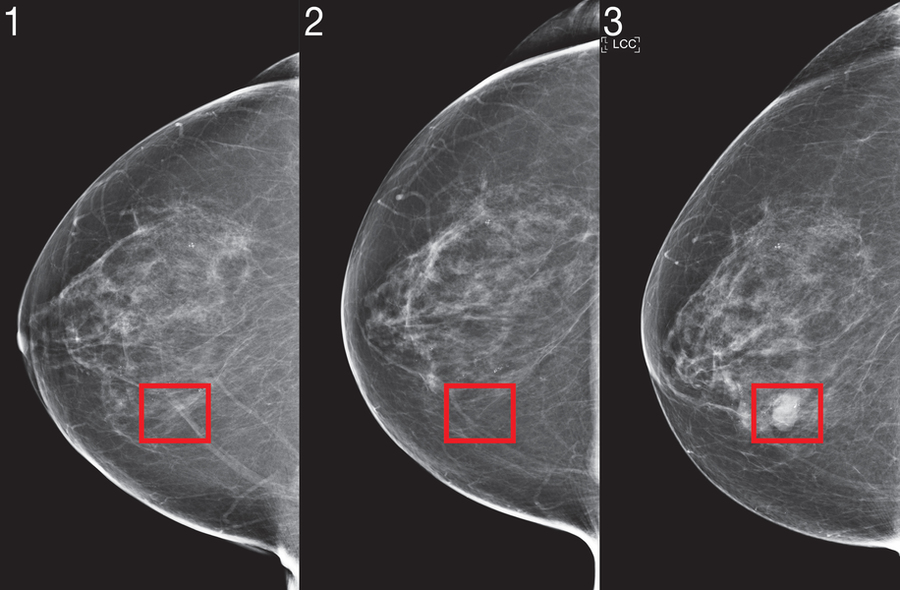

For deep-learning risk models to be integrated into clinical practice guidelines, they must demonstrate consistent performance across diverse healthcare environments, with predictions unaffected by minor variables such as specific mammography equipment manufacturers. Even within a single medical institution, the researchers discovered that conventional training methodologies failed to produce consistent predictions before and after mammography machine upgrades, as algorithms tended to learn environment-specific artifacts. To eliminate this bias, the team implemented an adversarial training scheme that specifically learns mammogram representations invariant to the clinical environment source, ensuring prediction consistency across diverse settings.

Mirai's operational methodology follows a sophisticated multi-stage process: Initially, the mammogram image undergoes processing through an advanced 'image encoder' that extracts meaningful features. Subsequently, each image representation, combined with information about its acquisition view, is integrated with other images from different perspectives to generate a comprehensive representation of the complete mammogram. Concurrently, the system predicts traditional risk factors using a Tyrer-Cuzick model framework (including variables such as age, body mass index, and hormonal factors)—employing predicted values when actual measurements are unavailable. Finally, utilizing this integrated information, the additive-hazard layer generates a patient's risk probability for each year over the subsequent five-year period.